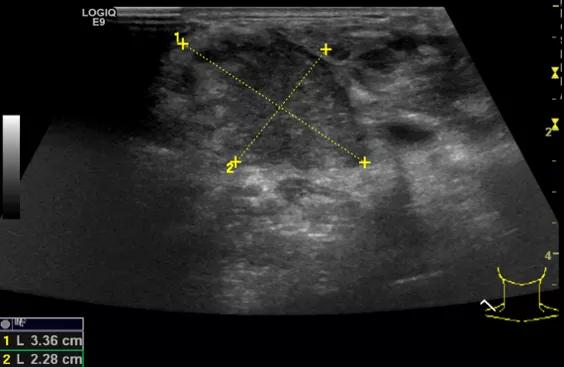

第三例是甲状腺癌患者,双侧甲状腺癌切除术后、碘治疗后一年余效果欠佳,超声显示左颈3区3枚低回声结节,穿刺示甲状腺乳头状癌转移。患者不愿意手术,希望采取局部治疗。对病灶进行液体隔离后采取热消融术,由于淋巴结较小,热消融一分钟左右完全灭活,术后增强影像显示没有脏器充填。

(病例3图例)